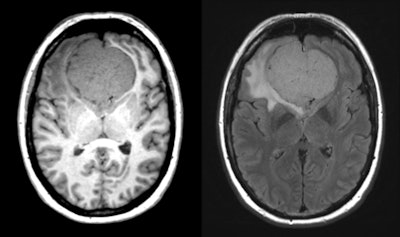

Example of an incidental finding in whole-body MR scan in population-based imaging without contrast enhancement showing an intracranial tumor mass -- T1-weighted isointense, T2-weighted slightly hyperintense, arising from the olfactory groove with significant local mass effect and moderate surrounding FLAIR signal hyperintensity within the left frontal lobe, most likely representing olfactory groove meningioma. Further workup and near-term neurosurgical consultation are necessary.

Example of an incidental finding in whole-body MR scan in population-based imaging without contrast enhancement showing an intracranial tumor mass -- T1-weighted isointense, T2-weighted slightly hyperintense, arising from the olfactory groove with significant local mass effect and moderate surrounding FLAIR signal hyperintensity within the left frontal lobe, most likely representing olfactory groove meningioma. Further workup and near-term neurosurgical consultation are necessary.Incidental finding reporting could pose a problem to logistics or participant well-being if a large body area is covered in high detail in great numbers of participants during a big population study, according to Schlett, speaking to AuntMinnieEurope.com in an interview after the RSNA 2017 meeting, where the results of the survey were presented. Other cohort studies are currently recruiting with sample sizes of 30,000 to 200,000 whole-body MRI scans, and incidental findings are likely to be high, he noted, raising the question of how to treat the findings in terms of both investigator reporting resources, and/or participant psychological burden.